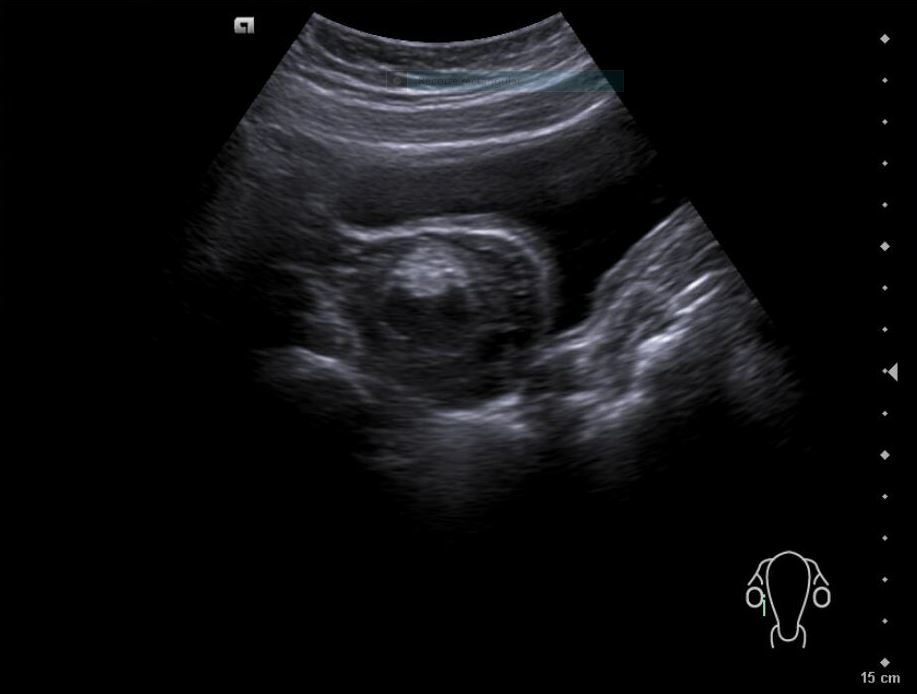

Descripción de los hallazgos ecográficos y las imágenes más relevantes para la resolución del caso

Diagnóstico inicial: Teratoma ovárico derecho versus cuerpo lúteo hemorrágico.

Diagnóstico diferencial: endometriosis, quiste funcional, quiste dermoide.

La paciente es valorada en consulta presencial de ginecología. Ecografía vaginal confirma: